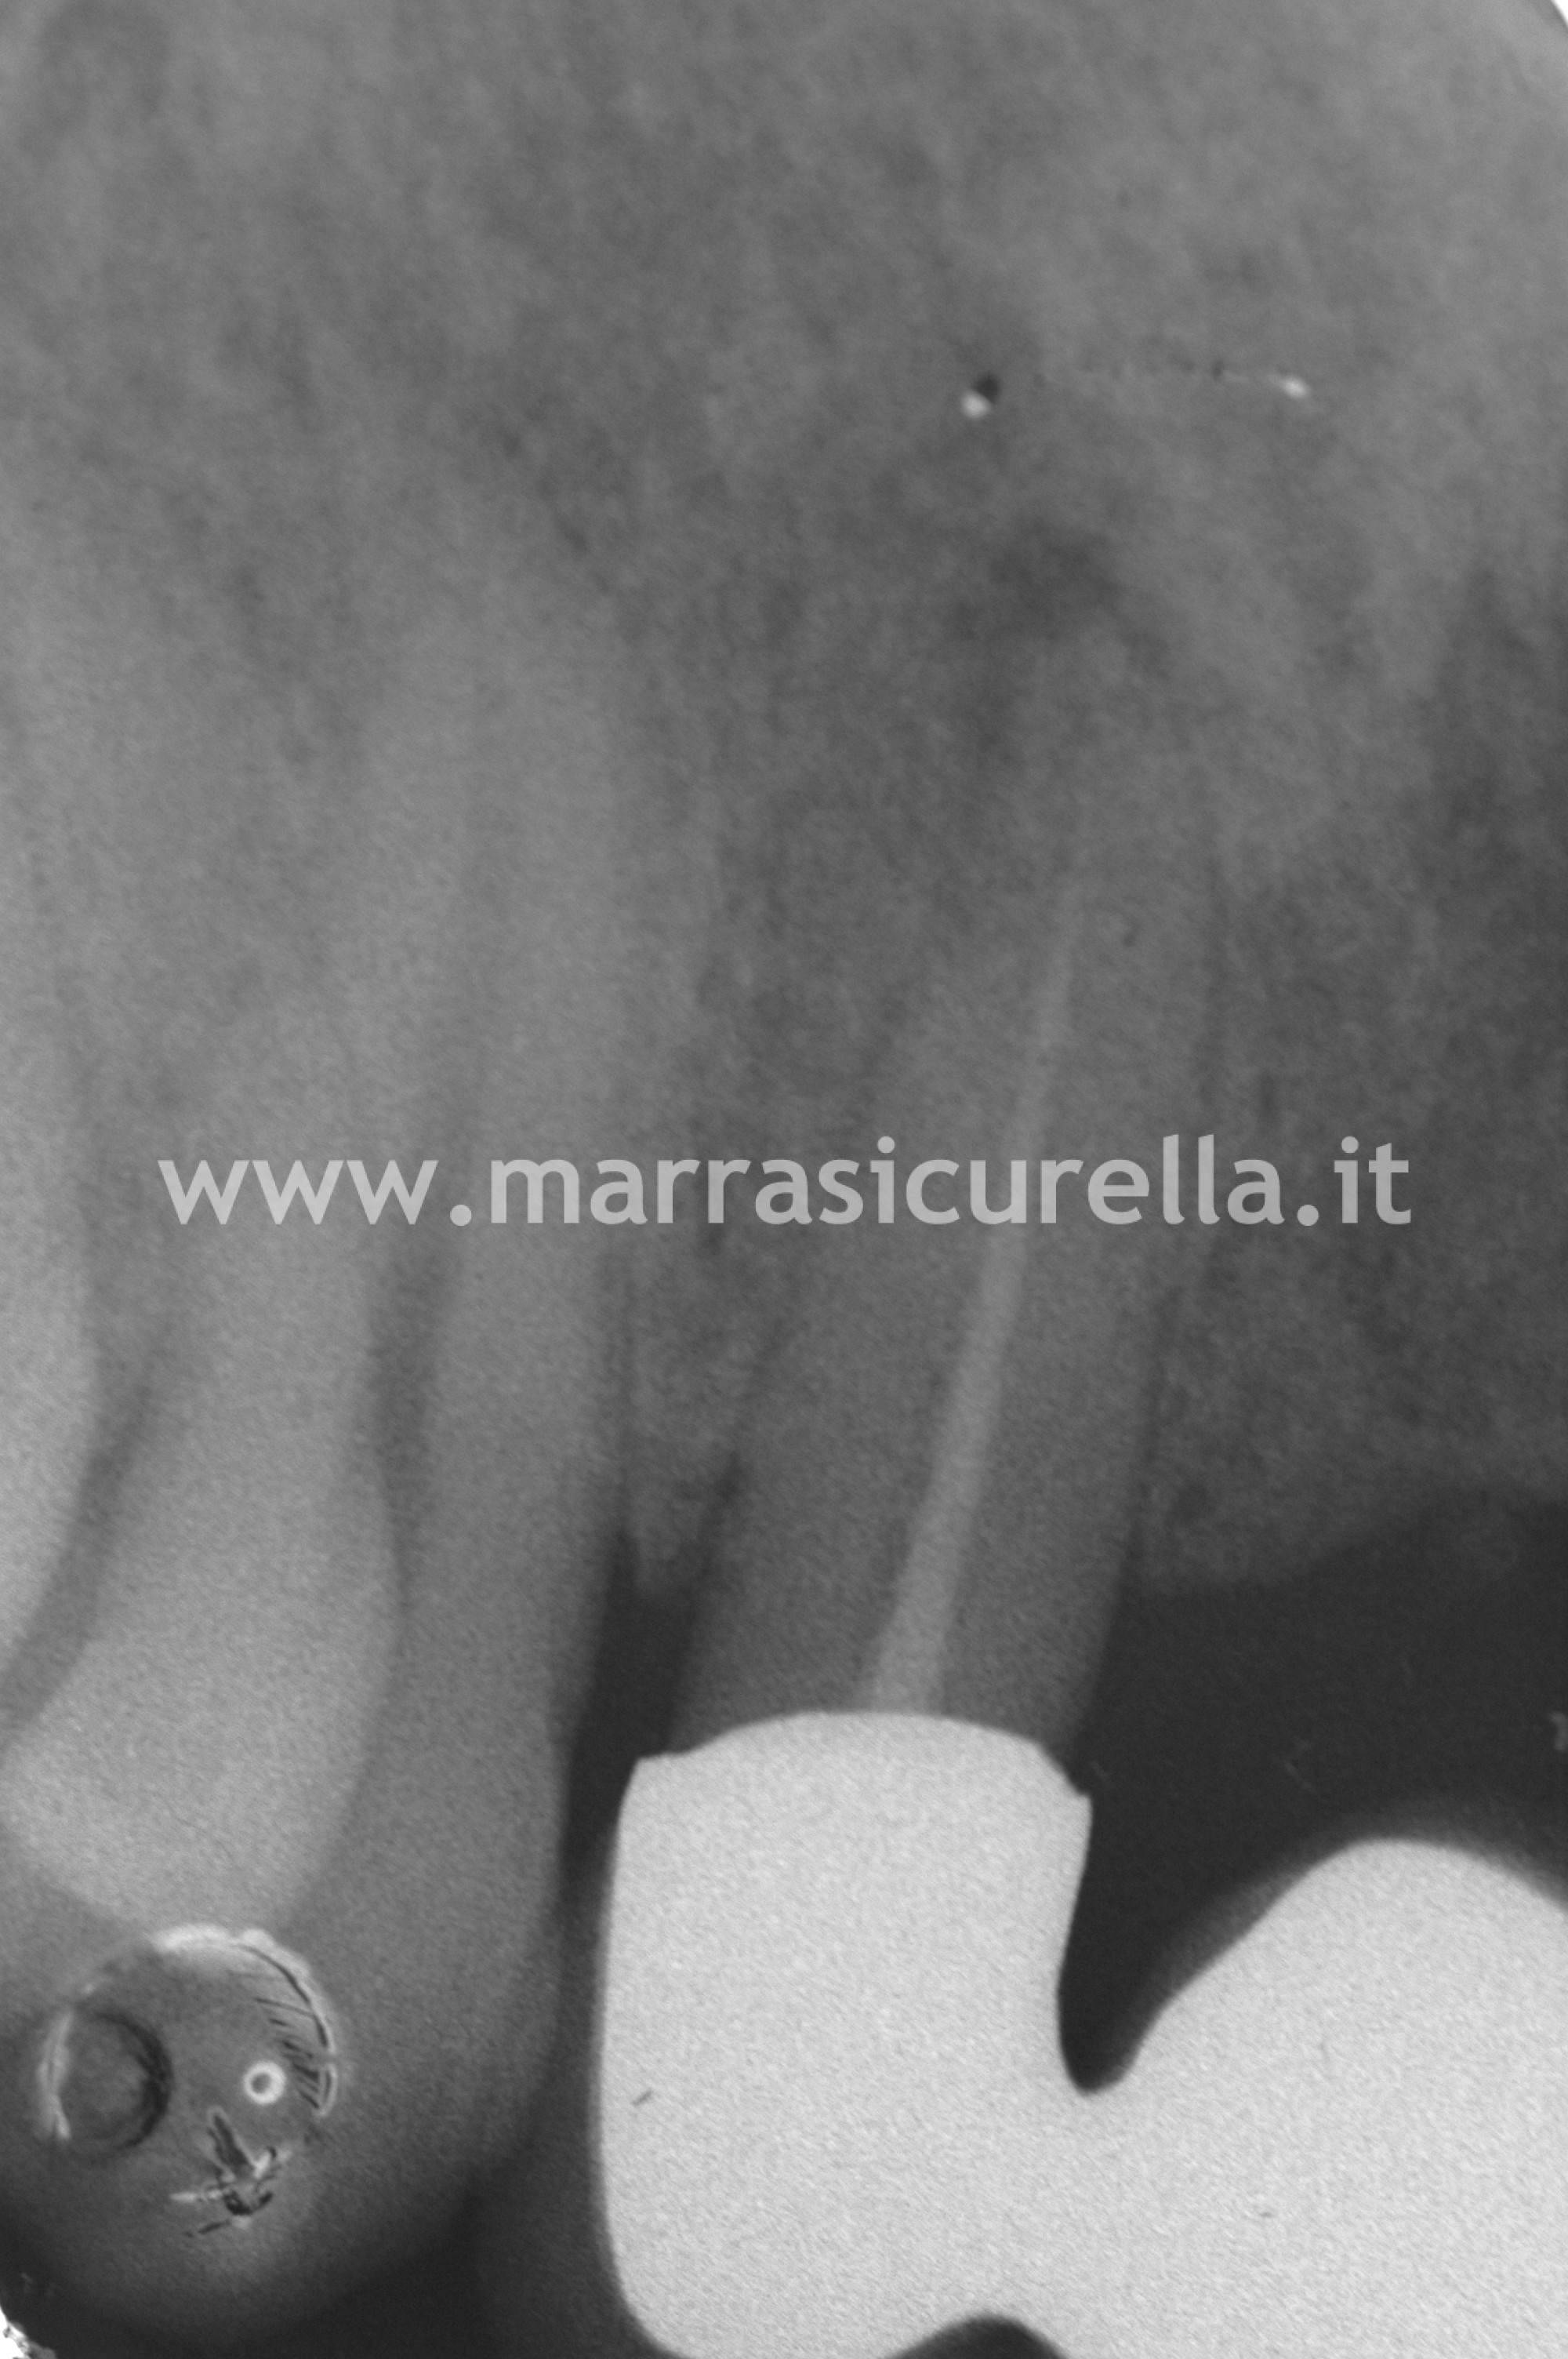

Una valutazione dell’esame dell’ortopantomografia metteva in evidenza numerose problematiche: grave parodontite (infiammazione delle gengive che risultavano sanguinanti), carie secondarie e pregresse terapie oramai incongrue.

L’esame parodontale ed il quadro completo dell’esame rx confermava la complessità del piano di trattamento.